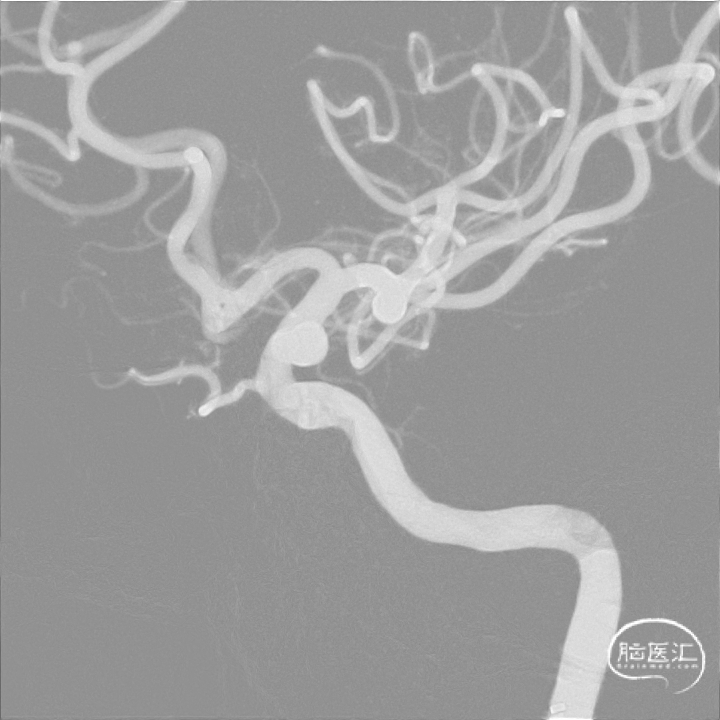

本次应治疗的动脉瘤为左侧颈内动脉眼动脉段动脉瘤。动脉瘤为囊状动脉瘤,结合动脉瘤形态学评估推断其破裂风险较低,可选择单纯应用血流导向密网支架进行治疗而无需弹簧圈栓塞,在降低手术难度的同时还可降低动脉瘤继续生长破裂和复发的风险。

造影确认FRED®血流导向密网支架打开良好,瘤内血流有滞留情况,支架整体贴壁良好。